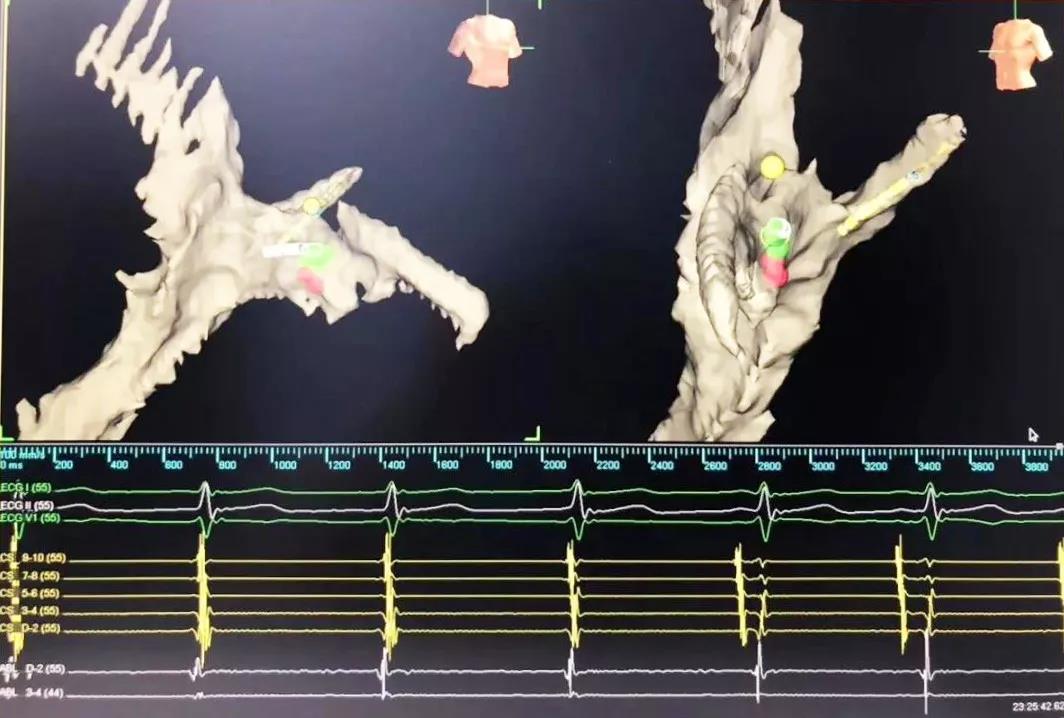

又一道難題擺在眼前,常規(guī)手術需要在X射線下進行,X射線會導致胎兒發(fā)育畸形。在心臟病醫(yī)院院長王海昌的帶領下,專家團隊仔細研究后,決定為張女士施行三維標測系統(tǒng)指引下零射線心臟電生理檢查及射頻消融術。

在完成常規(guī)檢查,排除新型冠狀病毒肺炎的可能后,217日,由廉誠主刀,在三維標測系統(tǒng)指引下行零射線心臟電生理檢查及射頻消融術。術中明確患者心動過速為房室結折返性心動過速,遂行房室結慢徑改良,消融完畢后反復刺激驗證,心動過速均不能誘發(fā),手術成功,歷時約1小時,全程零射線完成。這也是西安國際醫(yī)學中心醫(yī)院心臟病醫(yī)院的首例零射線治療特殊人群心律失常病例。